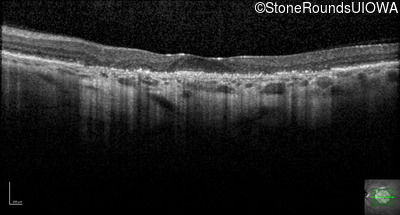

Optical Coherence Tomography - Left - 5/400

Exemplar / OCT Stack